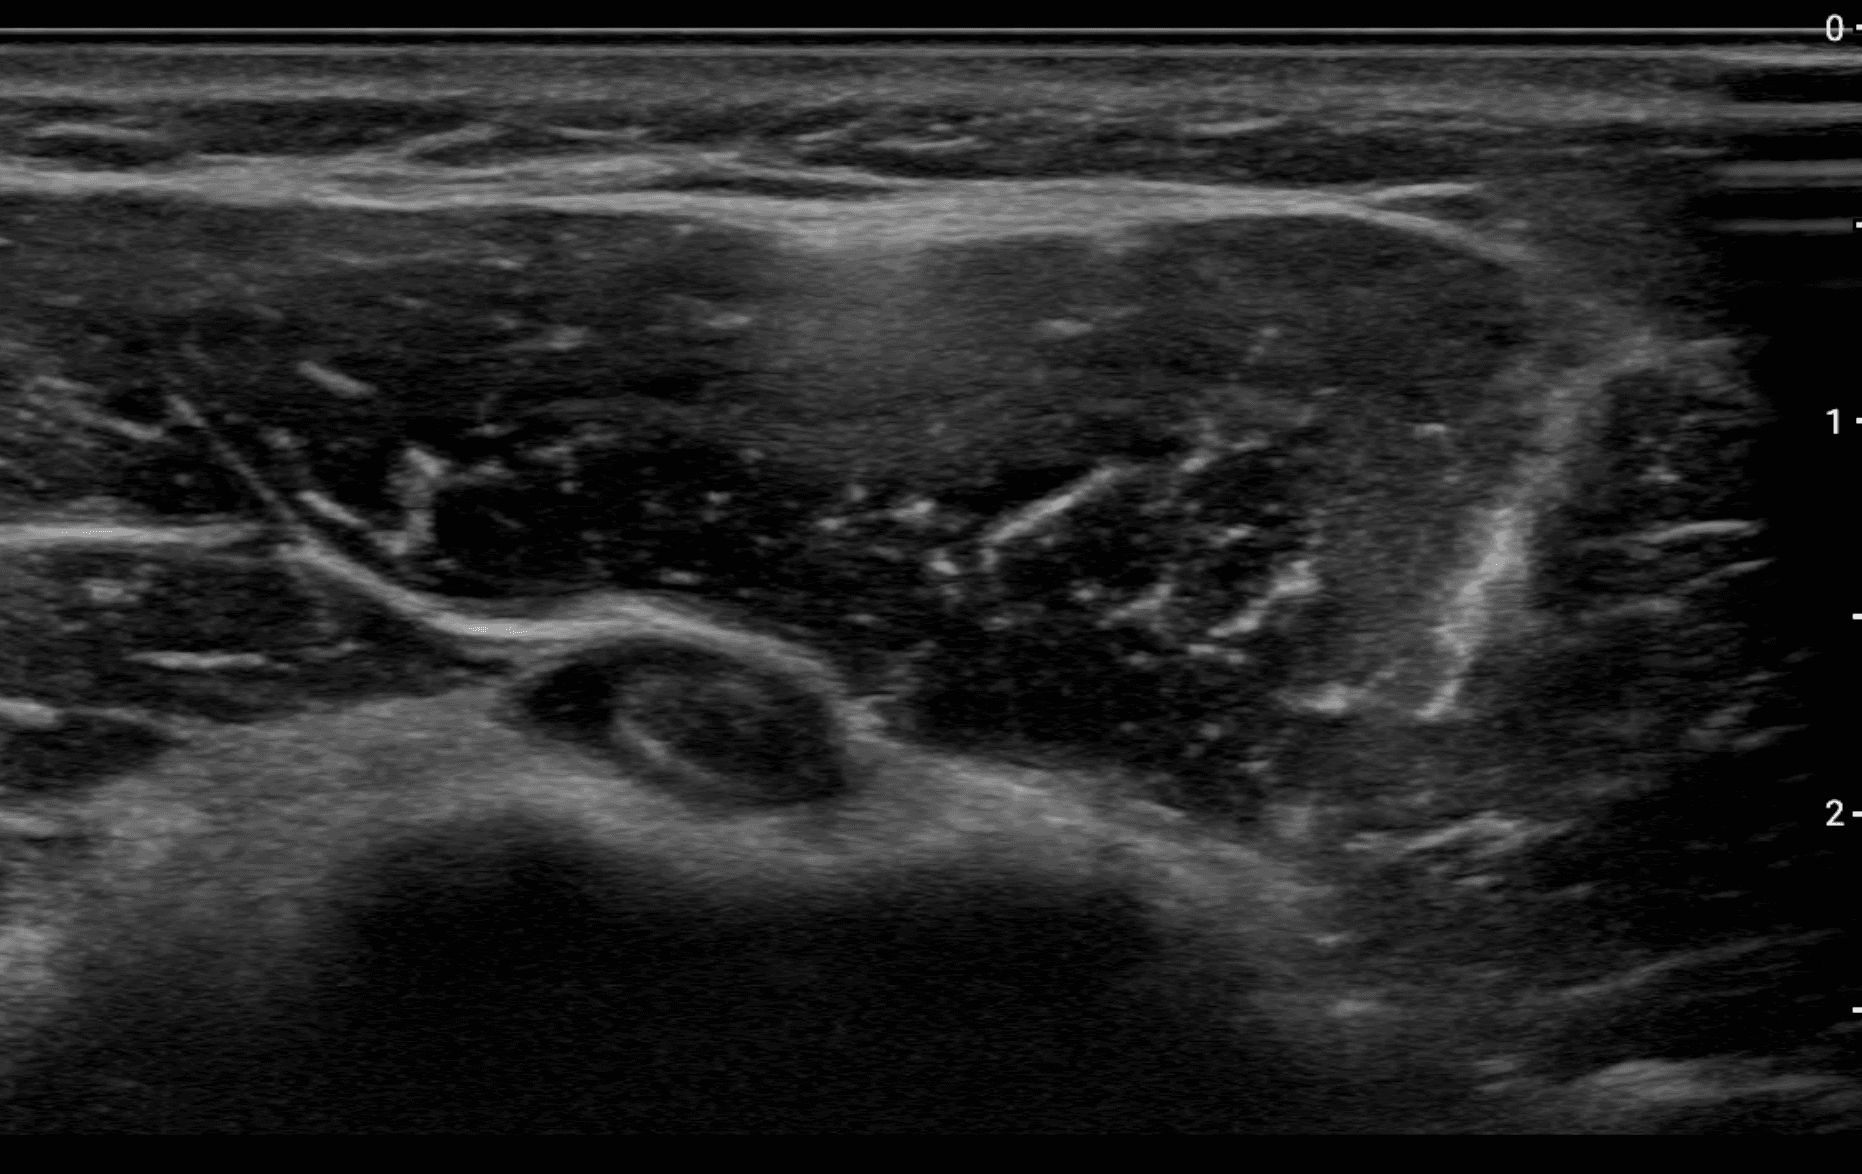

Master the use of ultrasound for diagnosing biceps tendon injuries, including both proximal and distal biceps tendon pathologies. This course provides an in-depth exploration of biceps tendon anatomy, injury patterns, and ultrasound imaging techniques for accurate diagnosis. Learn how to identify common injuries like tenosynovitis, tendinosis, tears, and biceps pulley injuries. Understand how to visualize the distal biceps tendon using advanced techniques like the Cobra Head and Pronator Window positions. Ideal for sonographers, radiologists, and orthopedic professionals, this course enhances your skills in using ultrasound as a reliable tool for diagnosing biceps tendon conditions, offering an effective alternative to MRI in many clinical settings.

Identify injuries of the proximal and distal biceps brachii tendons